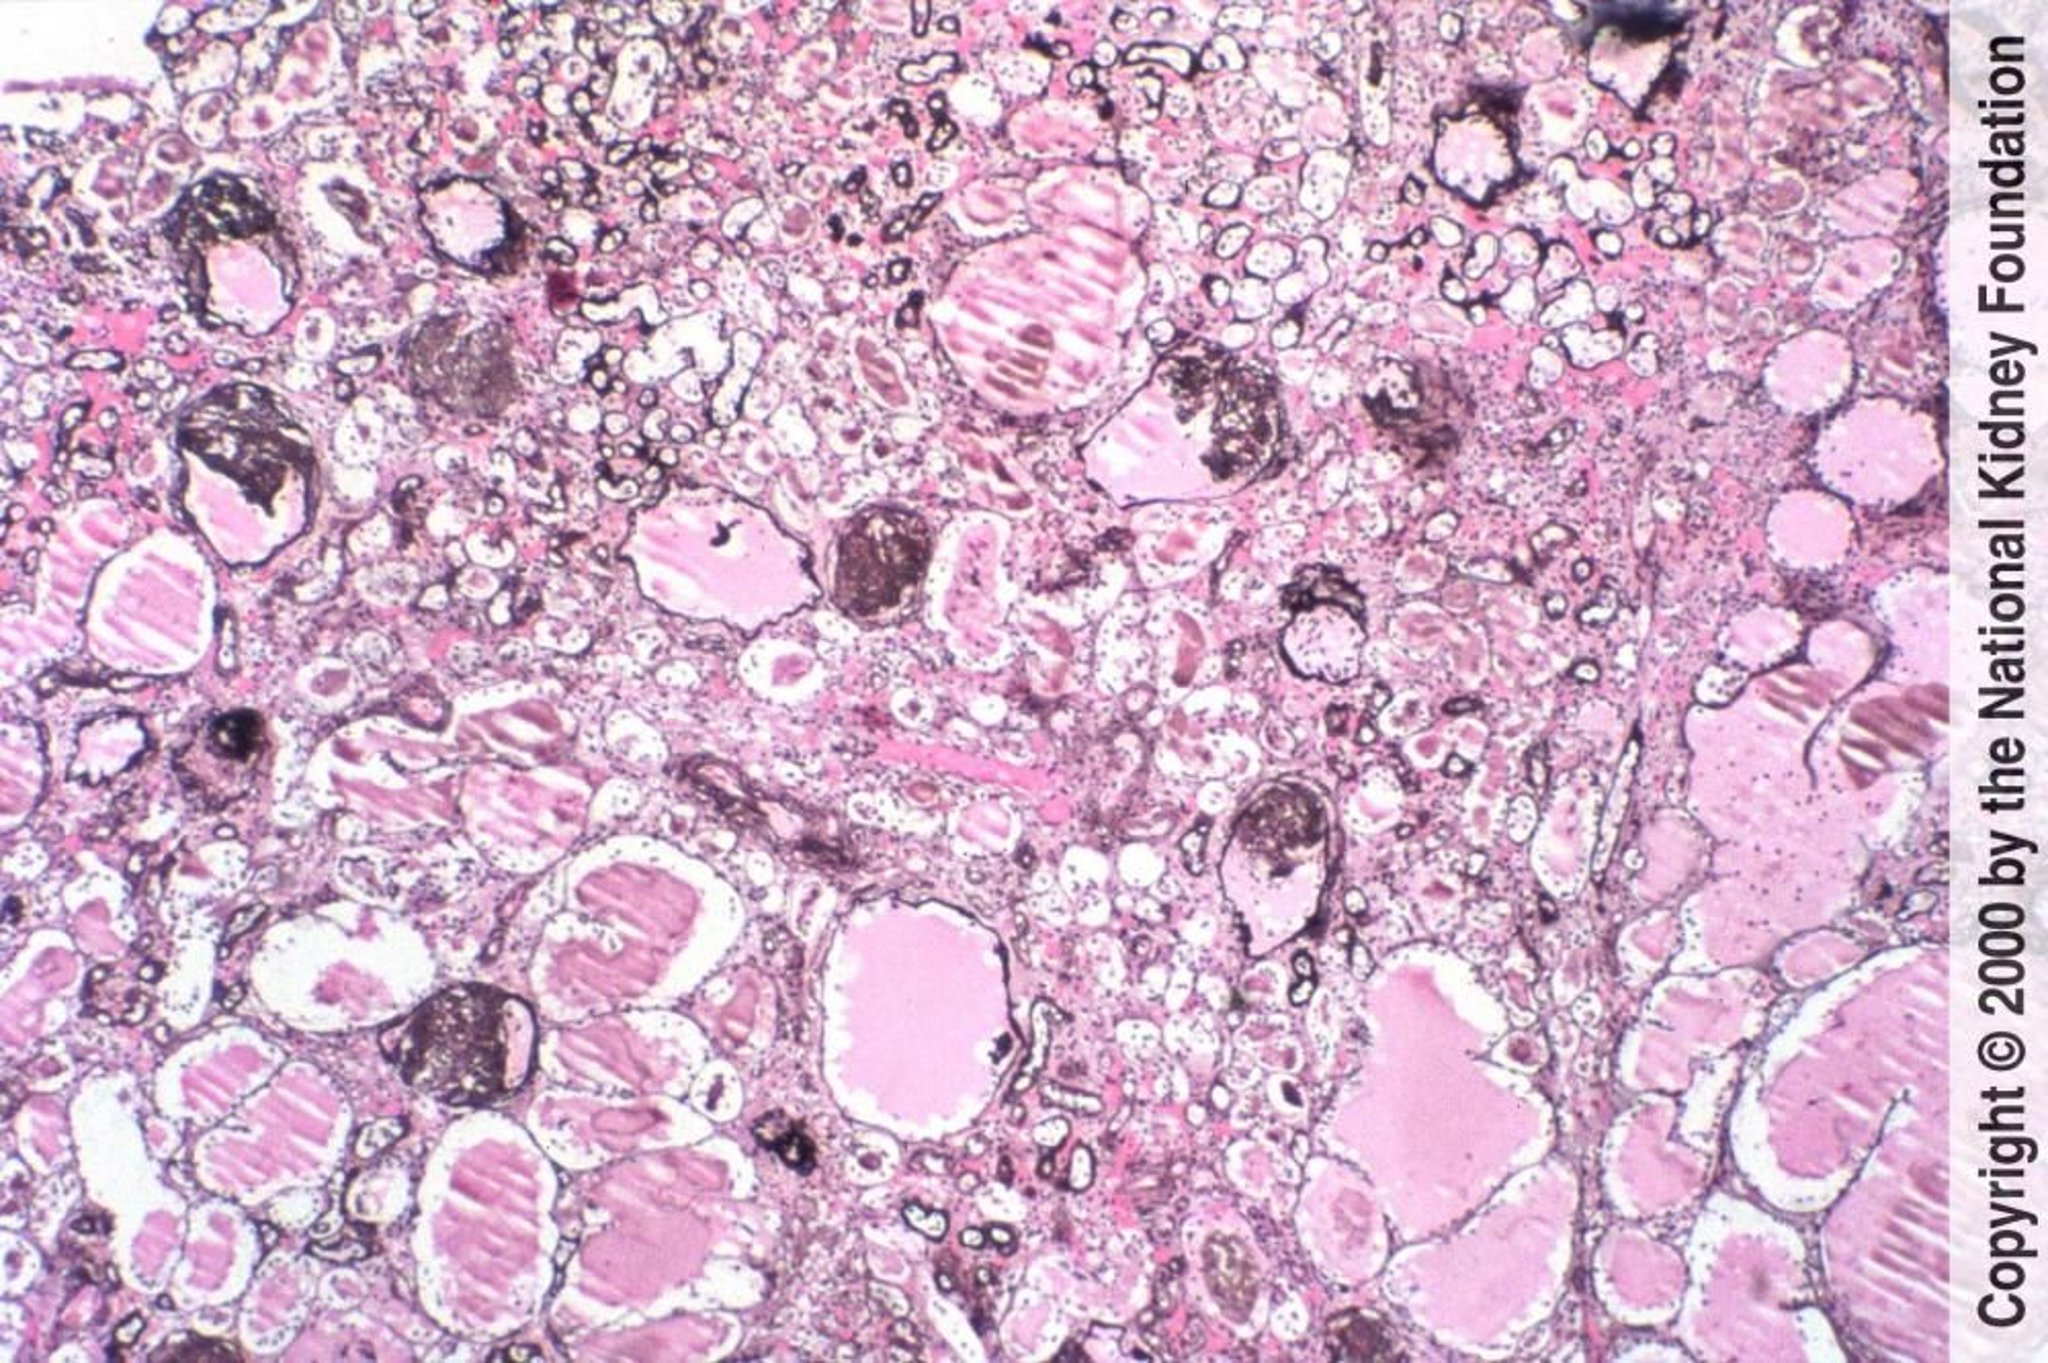

Néphropathie associée au VIH (Collapsing Glomerulopathy)

Une glomérulosclérose segmentaire et focale avec effondrement des glomérules et des anomalies tubulaires microcystiques est caractéristique de la néphropathie associée au VIH (coloration de Jones à l'argent, ×100).

Image fournie par Agnes Fogo, MD, and the American Journal of Kidney Diseases' Atlas of Renal Pathology (voir www.ajkd.org).